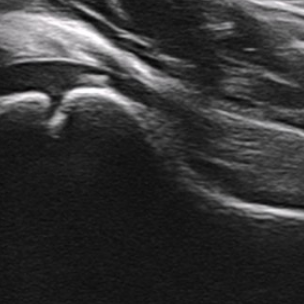

Identify this image.

Normal pediatric hip